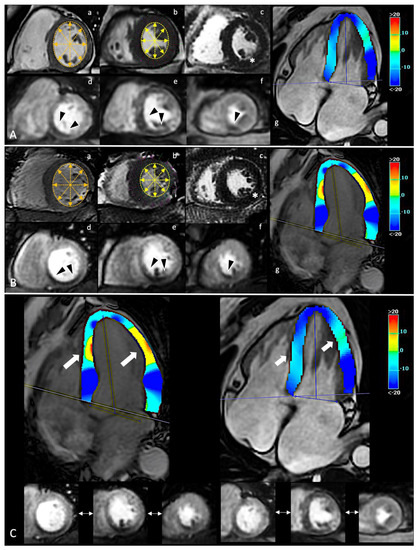

- CMR-related strain confirms its ability to stage myocardial damage, which could translate into a critical ability to predict disease progression [99,100]. Among CCS patients with ischemia and no other conventional imaging predictor, GLS resulted highly impaired with a good correlation with the ischemic burden. This correlation proves GLS (an indicator of global function) as effective in describing the real impact of ischemia on cardiac function beyond the localized distribution of ischemic damage [101].

- Despite GLS significantly differing between ischemic and non-ischemic CCS patients, GCS and GRS results were impaired when compared to a healthy population. Actually, in our series, GCS showed a stable early impairment compared to healthy volunteers. GCS impairment is indeed more likely related to a transmural injury/advanced disease, while GLS resulted most sensitive to a subendocardial/early injury [99]. On the other hand, the lack of a significant difference of GRS between ischemic and non-ischemic longstanding CCS patients could be explained by a relatively preserved compensating mechanism offered by circumferential fibers, since radial strain is tethered with other longitudinal and circumferential fibers and no radially oriented fibers are disposed within the myocardium.